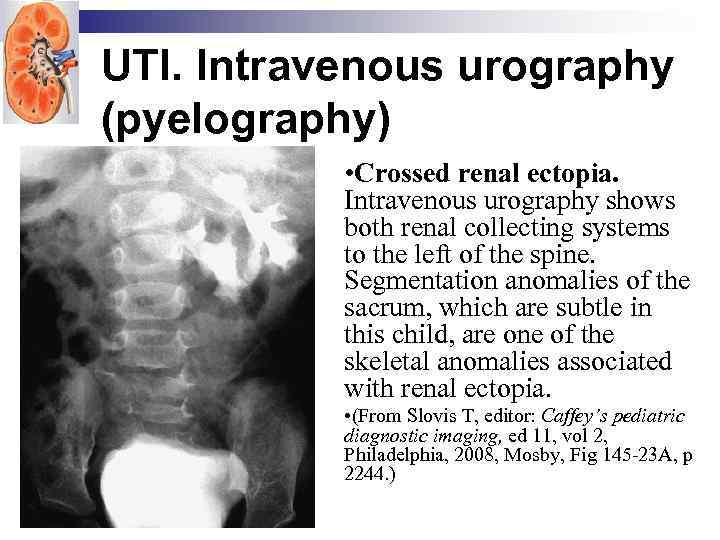

UTI. Intravenous urography (pyelography) • Crossed renal ectopia. Intravenous urography shows both renal collecting systems to the left of the spine. Segmentation anomalies of the sacrum, which are subtle in this child, are one of the skeletal anomalies associated with renal ectopia. • (From Slovis T, editor: Caffey’s pediatric diagnostic imaging, ed 11, vol 2, Philadelphia, 2008, Mosby, Fig 145 -23 A, p 2244. )

UTI. Intravenous urography (pyelography) • Crossed renal ectopia. Intravenous urography shows both renal collecting systems to the left of the spine. Segmentation anomalies of the sacrum, which are subtle in this child, are one of the skeletal anomalies associated with renal ectopia. • (From Slovis T, editor: Caffey’s pediatric diagnostic imaging, ed 11, vol 2, Philadelphia, 2008, Mosby, Fig 145 -23 A, p 2244. )